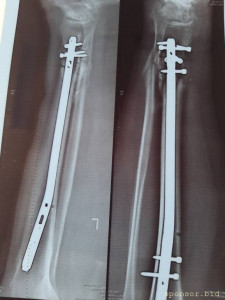

Вот что со мной произошло: летом прошлого 2022 года я неудачно упал, и сломал левую ногу, да так, что всё не закончлось просто гипсом. Перелом был сложным, пришлось делать операцию, ставить биос. Операция прошла с осложнениями, был свищ, нога после операции долго не заживала. Потом сломался крепёжный саморез, стало ещё хуже. Заболела правая нога в колене и бёдре. На приёме у врача сказали нужна операция! И в ближайшее время! Но я на больничном уже целый год, и после такого продолжительного лечения, все мои финансы на нуле. Ходить не могу, спать не могу, мучают постоянные боли. У меня развился сахарный диабет, ноги болят, появилась венозная недостаточность и варикоз. Мне всего 41 год. Получается я останусь инвалидом навсегда... Но у меня есть двое детей 5 и 14 лет... В данный момент я не могу встать на ноги из-за отсутствия финансовых средств. Моя мама Лариса Андреевна, помогает мне по мере своих сил. Ей приходится работать на производстве. Но ей уже 75 лет...

Нужна помощь сыну сотрудницы Не может ходить. - 20230719_135445.jpg

Нужна помощь сыну сотрудницы Не может ходить. - 20230719_135457.jpg